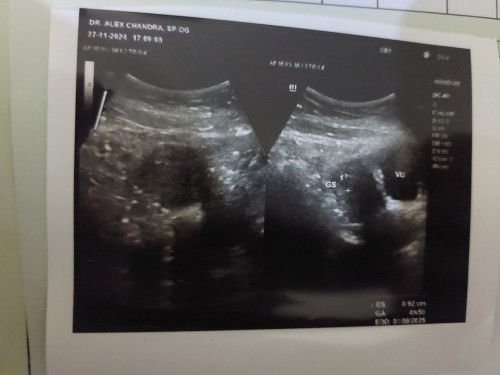

Hasil usg TM 1

USG tm 1, di usia kehamial menuju 5w, baru terlihat kantung kehamilan. Alhamdulillah #usgTM1